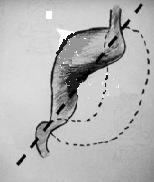

Volvulus de type

organo-axiale . Dans ce cas la grand courbure de

estoma en tortion180 degree autour sa axe |

mesenterico axiale |

Type mixte de volvulus

de estomac |